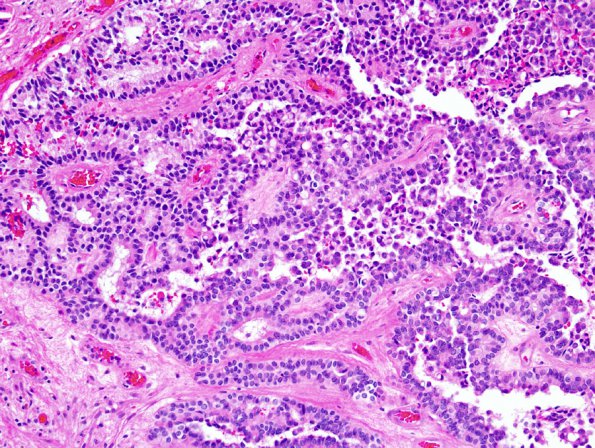

Papillary Tumor Pineal Region (PTPR)

3B3 Papillary Tumor Pineal Region (PTPR) (Case 3) 7.jpg

Higher magnification of the neoplasm (H&E)